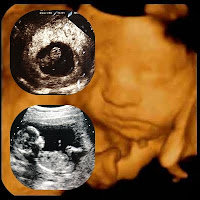

Íme a csinos kis pofija születendő leánykánknak. Nem olyan rég volt, hogy először hallotuk a szívverését, először láttuk, hogy kis hóember módjára integet nekünk. Aztán egyre közeledett a várva várt dátum.

2009. április 4-e amikor is betöltjük a 40. hetet. Valahogy a megérzés azt súgta, hogy 1-jén fog érkezni a mi kis bolondos tündérkénk.